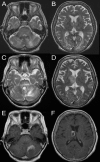

Figure 1. Brain magnetic resonance imaging of the patient.

A-B, T2-weighed imaging at initial presentation: (A) Hyperintense signal in the bilateral cerebellar hemispheres; (B) Hyperintensity noted in the bilateral thalamus and bioccipital subcortex; C-F, T2-weighted imaging and T1-weighted imaging with gadolinium enhancement immediately before brain biopsy; (C) Hyperintense lesions noted in the pons and the left side of the cerebellum; (D) Progression of the lesion of the thalamus on the right; (E) Ring-enhancing lesion of the cerebellum; (F) Ring-enhancing lesion of the thalamus.